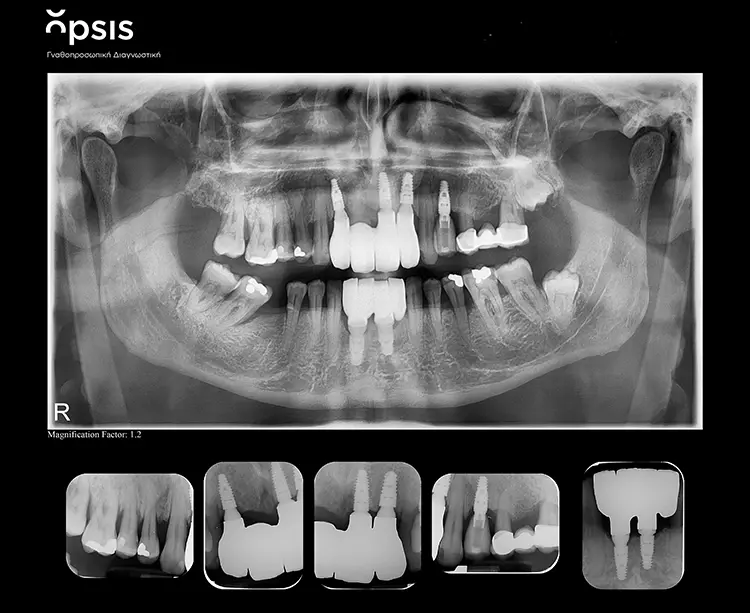

Nach Abschluss der Vorbehandlungsmaßnahmen erfolgte die Implantatinsertion in Lokalanästhesie (Artikamine 1:100.000, Adipharm, Griechenland) im Ober- und Unterkiefer-Frontzahnbereich in zwei getrennten Sitzungen. Im vorliegenden Fall war eine Sofortimplantation vorgesehen. Im Oberkiefer sollten drei Implantate inseriert werden, während im Unterkiefer aufgrund der eingeschränkten Platzverhältnisse zwei Implantate verwendet werden sollten.

Die Implantatinsertion erfolgte freihändig ohne vorherige digitale Planung oder Einsatz einer Bohrschablone. Im Oberkiefer wurden in die Extraktionsalveolen der Zähne 12, 21 und 22 drei BEGO Semados RS-Implantate (BEGO Implant Systems GmbH & Co. KG, Bremen, Deutschland) mit einer Länge/einem Durchmesser von 4,1/10,0 mm (regio 12), 4,1/11,5 mm (regio 21) und 4,5/10,0 mm (regio 22) eingesetzt. Die Insertion der beiden Implantate im Unterkiefer (BEGO Semados RS 4,1/10,0 mm) erfolgte nicht exakt in die Extraktionsalveolen der nicht erhaltungswürdigen Zähne, sondern in einem Abstand von 4,0 mm zueinander und zu den natürlichen Zähnen 33 und 43.

Die Restaurationen fügten sich sowohl klinisch als auch ästhetisch durch ihre spezielle Charakterisierung in die bestehende Patientensituation ein (Abb. 13-15). Auch röntgenologisch konnte eine gute Passform ermittelt werden (Abb. 16).

Der fehlende Zahn 24 wurde ebenfalls mittels eines Semados RS Implantats (BEGO Implant Systems GmbH & Co. KG) mit einer Länge/einem Durchmesser von 4,1/10,0 mm und einer monolithischen Zirkonoxidkrone ersetzt (3D Pro). Die klinische Situation konnte im Rahmen einer Nachuntersuchung im September 2022, fast zweieinhalb Jahre nach der Versorgung im Mai 2020 als sehr gut bezeichnet werden (Abb. 17-20).